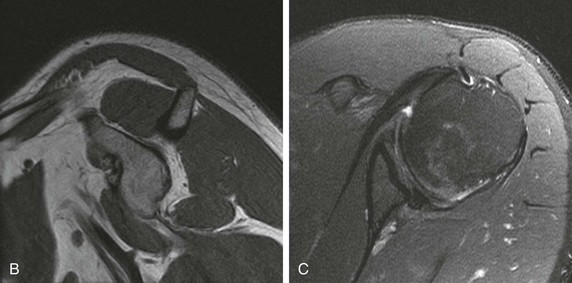

The “hourglass” biceps tendon describes a condition featuring marked tendinosis and hypertrophy isolated to the intraarticular portion of the long bicipital tendon, which prevents the tendon from sliding into the bicipital groove during elevation of the arm.131 Entrapment of the long bicipital tendon causes a mechanical block and pain. This condition occurs most often in association with a full-thickness tear of the rotator cuff, although entrapment occurring in association with partial-thickness rotator cuff tears has been described in case reports as well. Patients present with anterior arm pain and loss of passive elevation of the arm averaging about 10 to 20 degrees. The condition is treated with resection of the abnormal segment and tenodesis of the biceps tendon followed by appropriate treatment of any concomitant injury of the rotator cuff. MRI will show marked tendinosis and thickening limited to the intraarticular portion of the biceps tendon (Fig. 44-33) and is often associated with either a partial- or full-thickness rotator cuff tear.

Although conventional MRI is established as the imaging modality of choice in the evaluation of shoulder impingement syndrome, MRA is accepted as the method of choice for the evaluation of glenohumeral instability.22,23 Many of the lesions associated with instability are subtle and may undergo partial healing. This situation, coupled with the fact that the normal anatomic structures of the shoulder lie in close proximity, can make the diagnosis of these lesions difficult even with high-quality conventional MRI.58-62 MRA, on the other hand, is performed by distending the joint with fluid (saline solution or dilute gadolinium), which more accurately depicts subtle labral tears, cartilage and ligamentous abnormalities, and partial-thickness tears of the undersurface of the rotator cuff. The standard injection technique for MRA of the shoulder is described in previous sections. About 12 to 14 mL of gadolinium diluted 1 : 200 with normal saline solution or 1% lidocaine is injected. Imaging protocols vary, but a standard set of imaging sequences typically includes T1-weighted images with frequency-selective fat saturation in the axial, oblique sagittal, and oblique coronal planes. The T1-weighted images have a high signal/noise ratio, resulting in the anatomic detail that is critical in detecting the subtle lesions associated with glenohumeral instability. A T2-weighted sequence performed in the oblique coronal plane is the most important sequence for depicting rotator cuff abnormalities. A T2-weighted sequence may also be helpful in detecting other pathologic processes, such as a paralabral cyst or bone marrow edema (Fig. 44-7, A and B). The ABER view may be added to the standard imaging protocol for any patient thought to have an anterior labral pathologic process.54